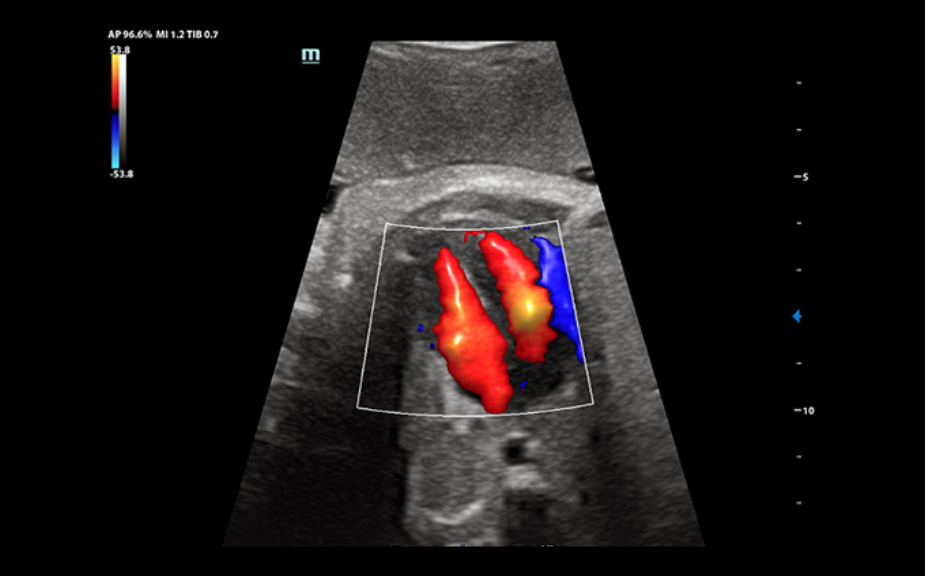

Obrazy kliniczne